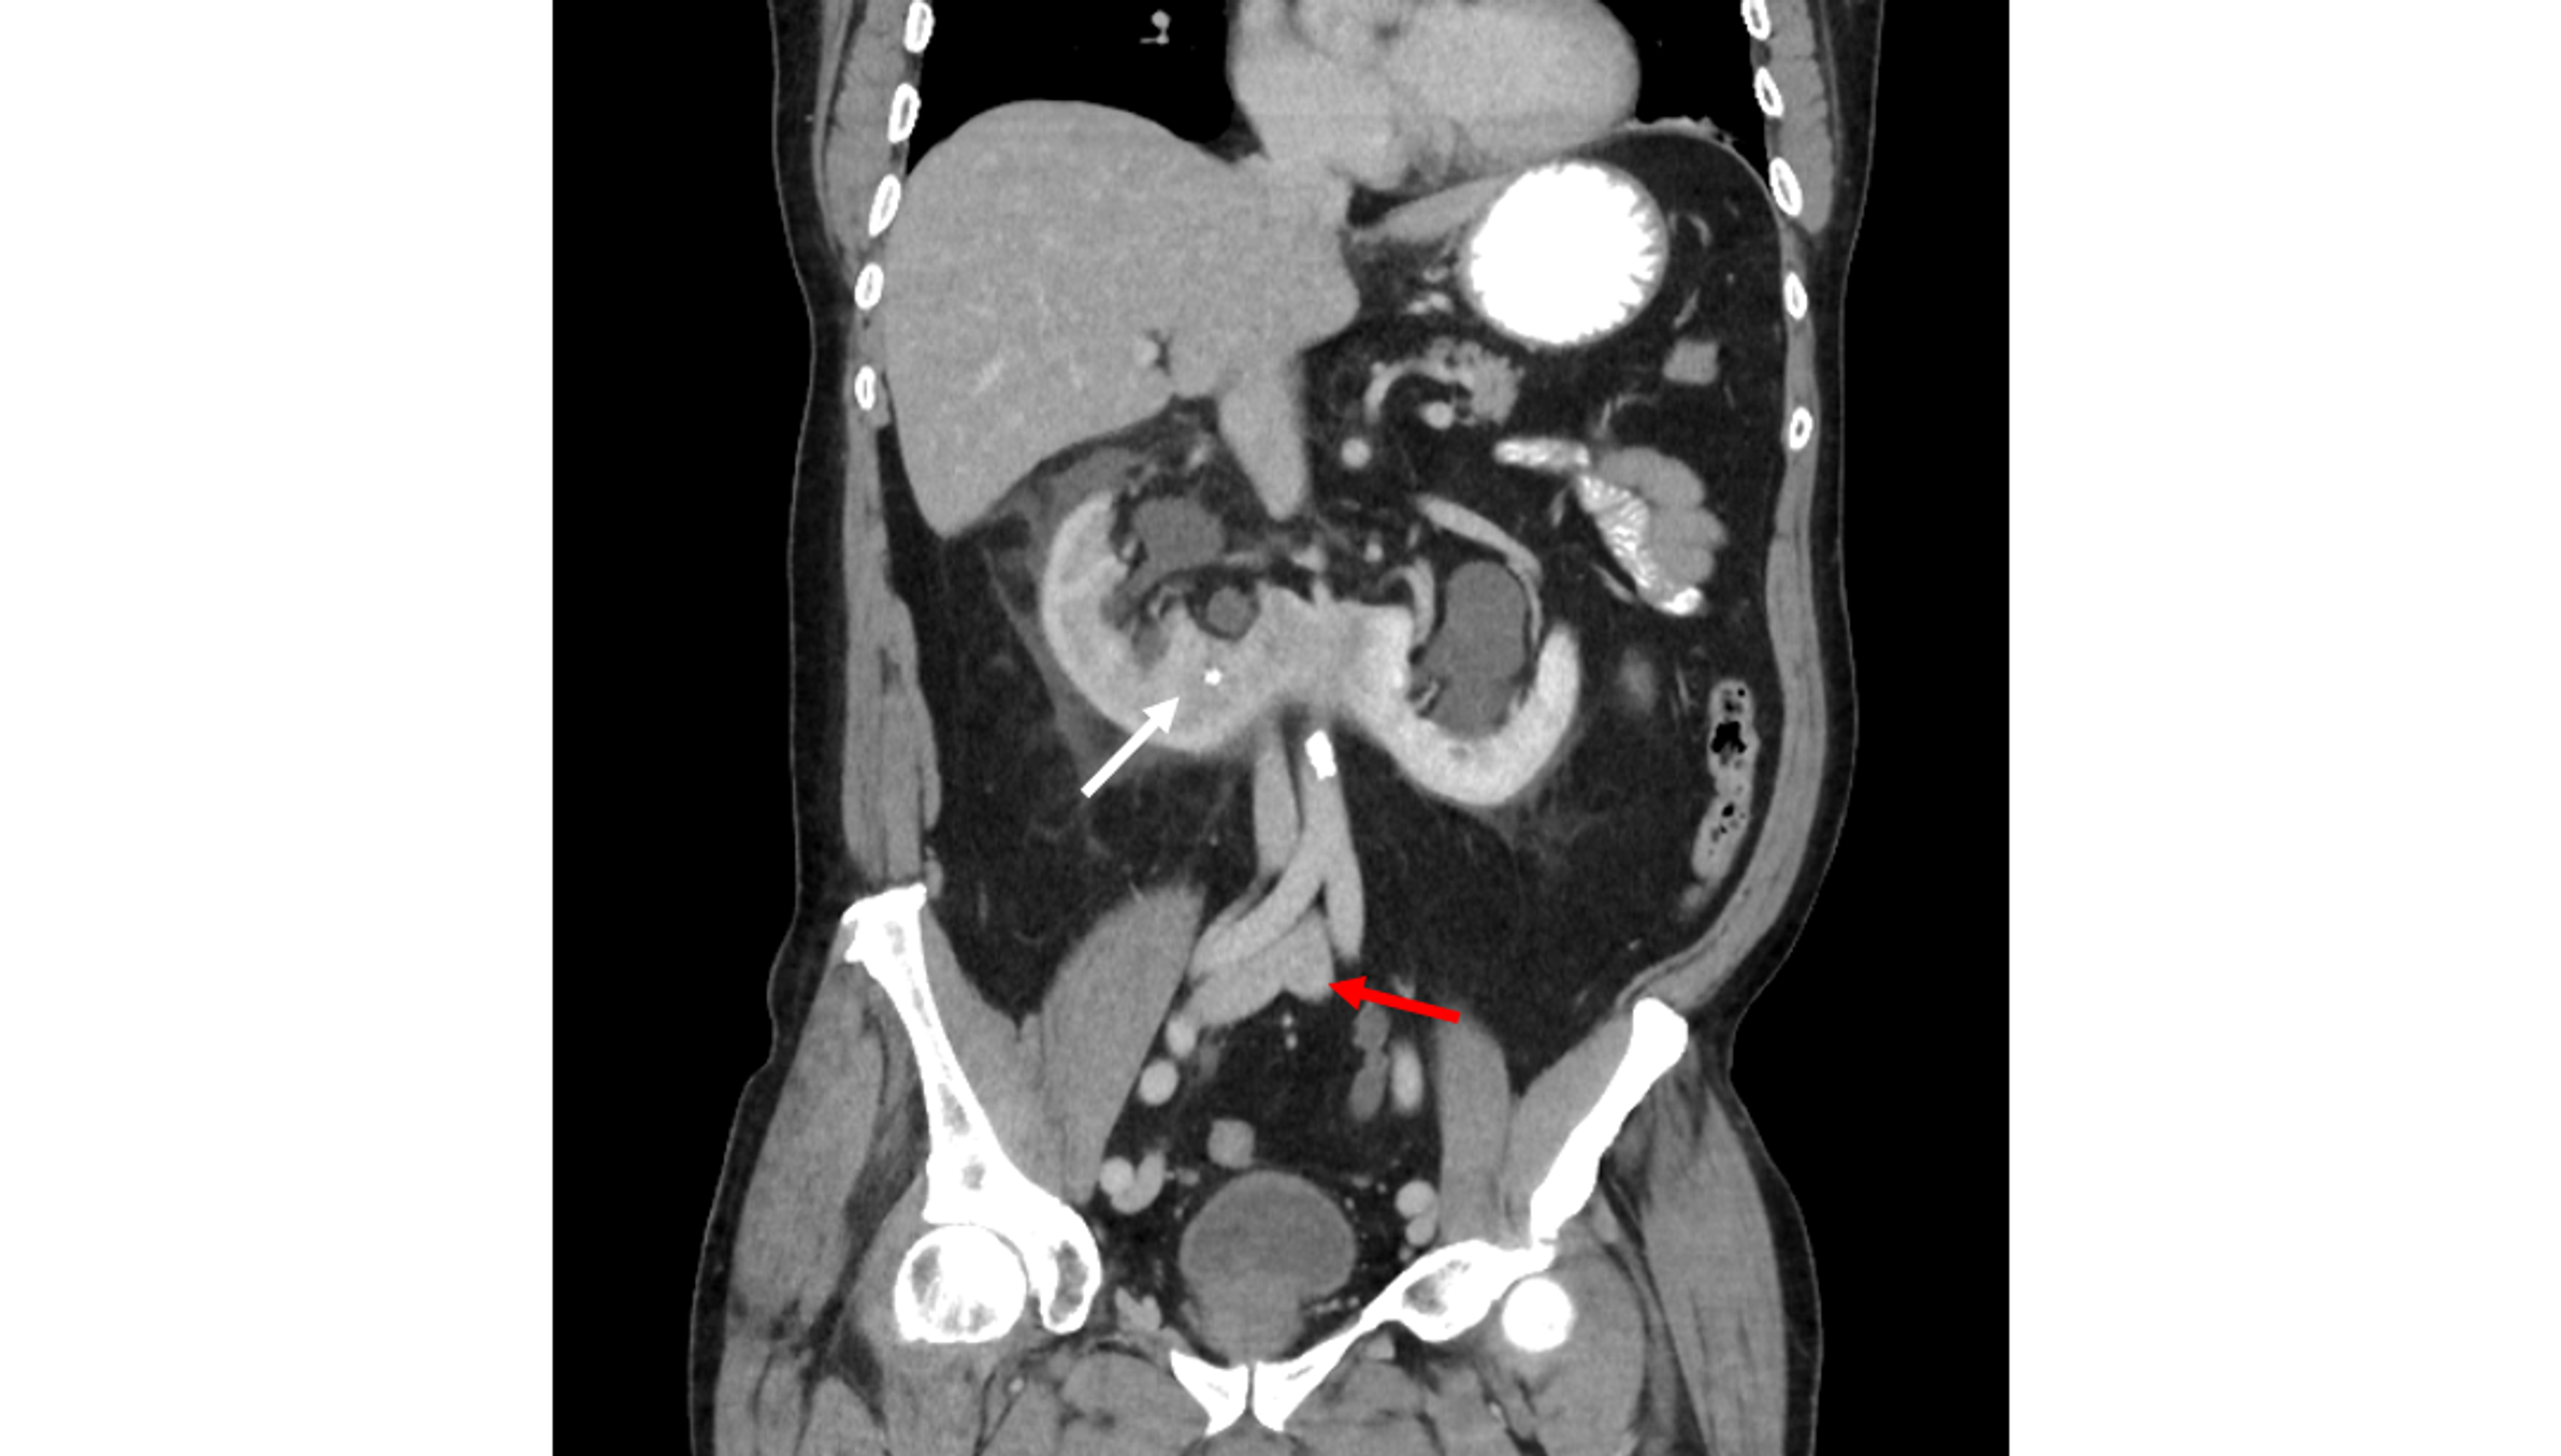

Coronal view of the patient's initial CT scan, demonstrating a 1.3cm Horseshoe Kidney Ct Scan The renal hila are rotated anateriology. Ct demonstrates the kidneys to be fused at their lower pole, located abnormally inferiorly immediately below the inferior mesenteric artery. Urogram protocol computed tomography (ct scanning of the abdomen and pelvis, with and without intravenous contrast) is. Horseshoe kidneys can be identified using most abdominal imaging modalities. Meanwhile, due to the concern regarding the. Horseshoe Kidney Ct Scan.

Horseshoe Kidney Ct Scan . Meanwhile, due to the concern regarding the abnormal relationship between the hsk and abdominal viscera, particularly the. It is often an incidental finding. Horseshoe kidneys can be identified using most abdominal imaging modalities. Its appearance is classic on ct and confirmatory tests are not necessary. Ct demonstrates the kidneys to be fused at their lower pole, located abnormally inferiorly immediately below the inferior mesenteric artery. The renal hila are rotated anateriology. Intravenous urography (ivu), computed tomography (ct) scanning, magnetic resonance imaging (mri), and scintigraphy. Urogram protocol computed tomography (ct scanning of the abdomen and pelvis, with and without intravenous contrast) is. Courtesy of laurence baskin, md. Unenhanced computed tomographic scan of horseshoe kidney with bilateral calculi. Horseshoe kidney is one form of several congenital renal anomalies.